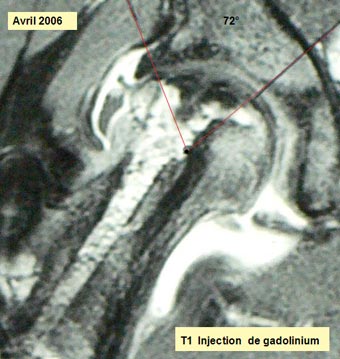

Imagerie préopératoire I.R.M.N.

Justification de la méthode Le traitement de l'ostéonécrose aseptique par autogreffe de moelle osseuse repose sur l'hypothèse que les cellules de la lignée ostéogénique dérivent d'une cellule souche initiatrice du stroma médullaire appelée CFU-F ou « Colony Forming Unit Fibroblastic ». On sait qu'il y a un appauvrissement cellulaire de la moelle osseuse dans l' ONANT. Deux techniques chirurgicales ont été proposées. La greffe de moelle osseuse pour augmenter le nombre de progéniteurs osseux situés dans la tête fémorale et dans la région trochantérienne. L'apport d'os spongieux que Steinberg a proposé de prélever au niveau de l'extrémité supérieure de la métaphyse fémorale. La question est : y a t-il à ce niveau un stock de cellules-souches suffisant ? Bien que la technique de greffe de moelle osseuse soit réservée aux stades I et II de la nécrose, nous avons proposé une intervention associant une résection de la nécrose et un comblement-greffe de la zone nécrotique à l'aide d'un composite : mélange de substitut osseux imprégné de moelle osseuse. Pourquoi ? Au stade III, contrairement au stade I et II, il n' y a pas de réversibilité spontanée possible, il ne paraît donc pas suffisant de se limiter à l'injection de la moelle osseuse sans nettoyer cette cavité en excisant la zone de nécrose. Dans le but de limiter l'écrasement responsable de la perte de la sphéricité de la tête fémorale, il est logique d'apporter « in situ » un matériau biologique mécaniquement résistant qui comble l'espace vide conjointement à l'adjonction du facteur biologique. La justification de cette proposition tient enfin au fait que l'étendue de la nécrose (95°) rend l'ostéotomie inter-trochantérienne très problématique sur le plan technique. En cas d'échec du comblement-greffe, il n'y aura aucune difficulté supplémentaire pour réaliser cette ostéotomie.